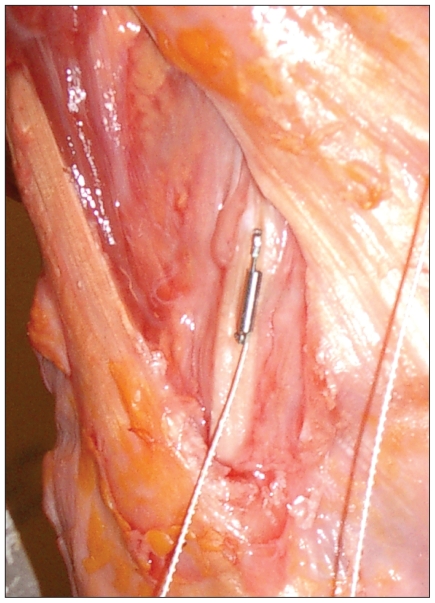

Strain measurement protocol

Differential variance reluctance transducers (DVRTs; Microstrain) were secured to the ACL, MCL, LCL and PCL to quantify ligament load in terms of strain (Fig. 2). The ACL strain gauge was positioned on the anteromedial bundle of the midsubstance. The anteromedial bundle was chosen to allow for comparisons between previously published experimental designs on ACL strain characteristics.17,19,20 The other strain gauges were secured to the posteromedial bundle of the PCL midsubstance, the superficial MCL at the level of the joint line, and the LCL at the level of the joint line. The specimens were placed in the experimental position, and the gauge locations were verified. In particular, the ACL strain gauge was checked for the absence of impingement in the intercondylar notch. A prophylactic minimal notchplasty was performed for each specimen before gauge insertion to limit the possibility of ACL gauge impingement.

Fig. 2.

Placement of a differential variance reluctance transducer strain gauge on the lateral collateral ligament.